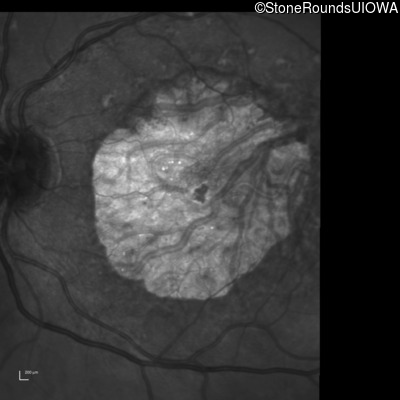

Infrared Fundus Photograph - Left - 20/125

Exemplar